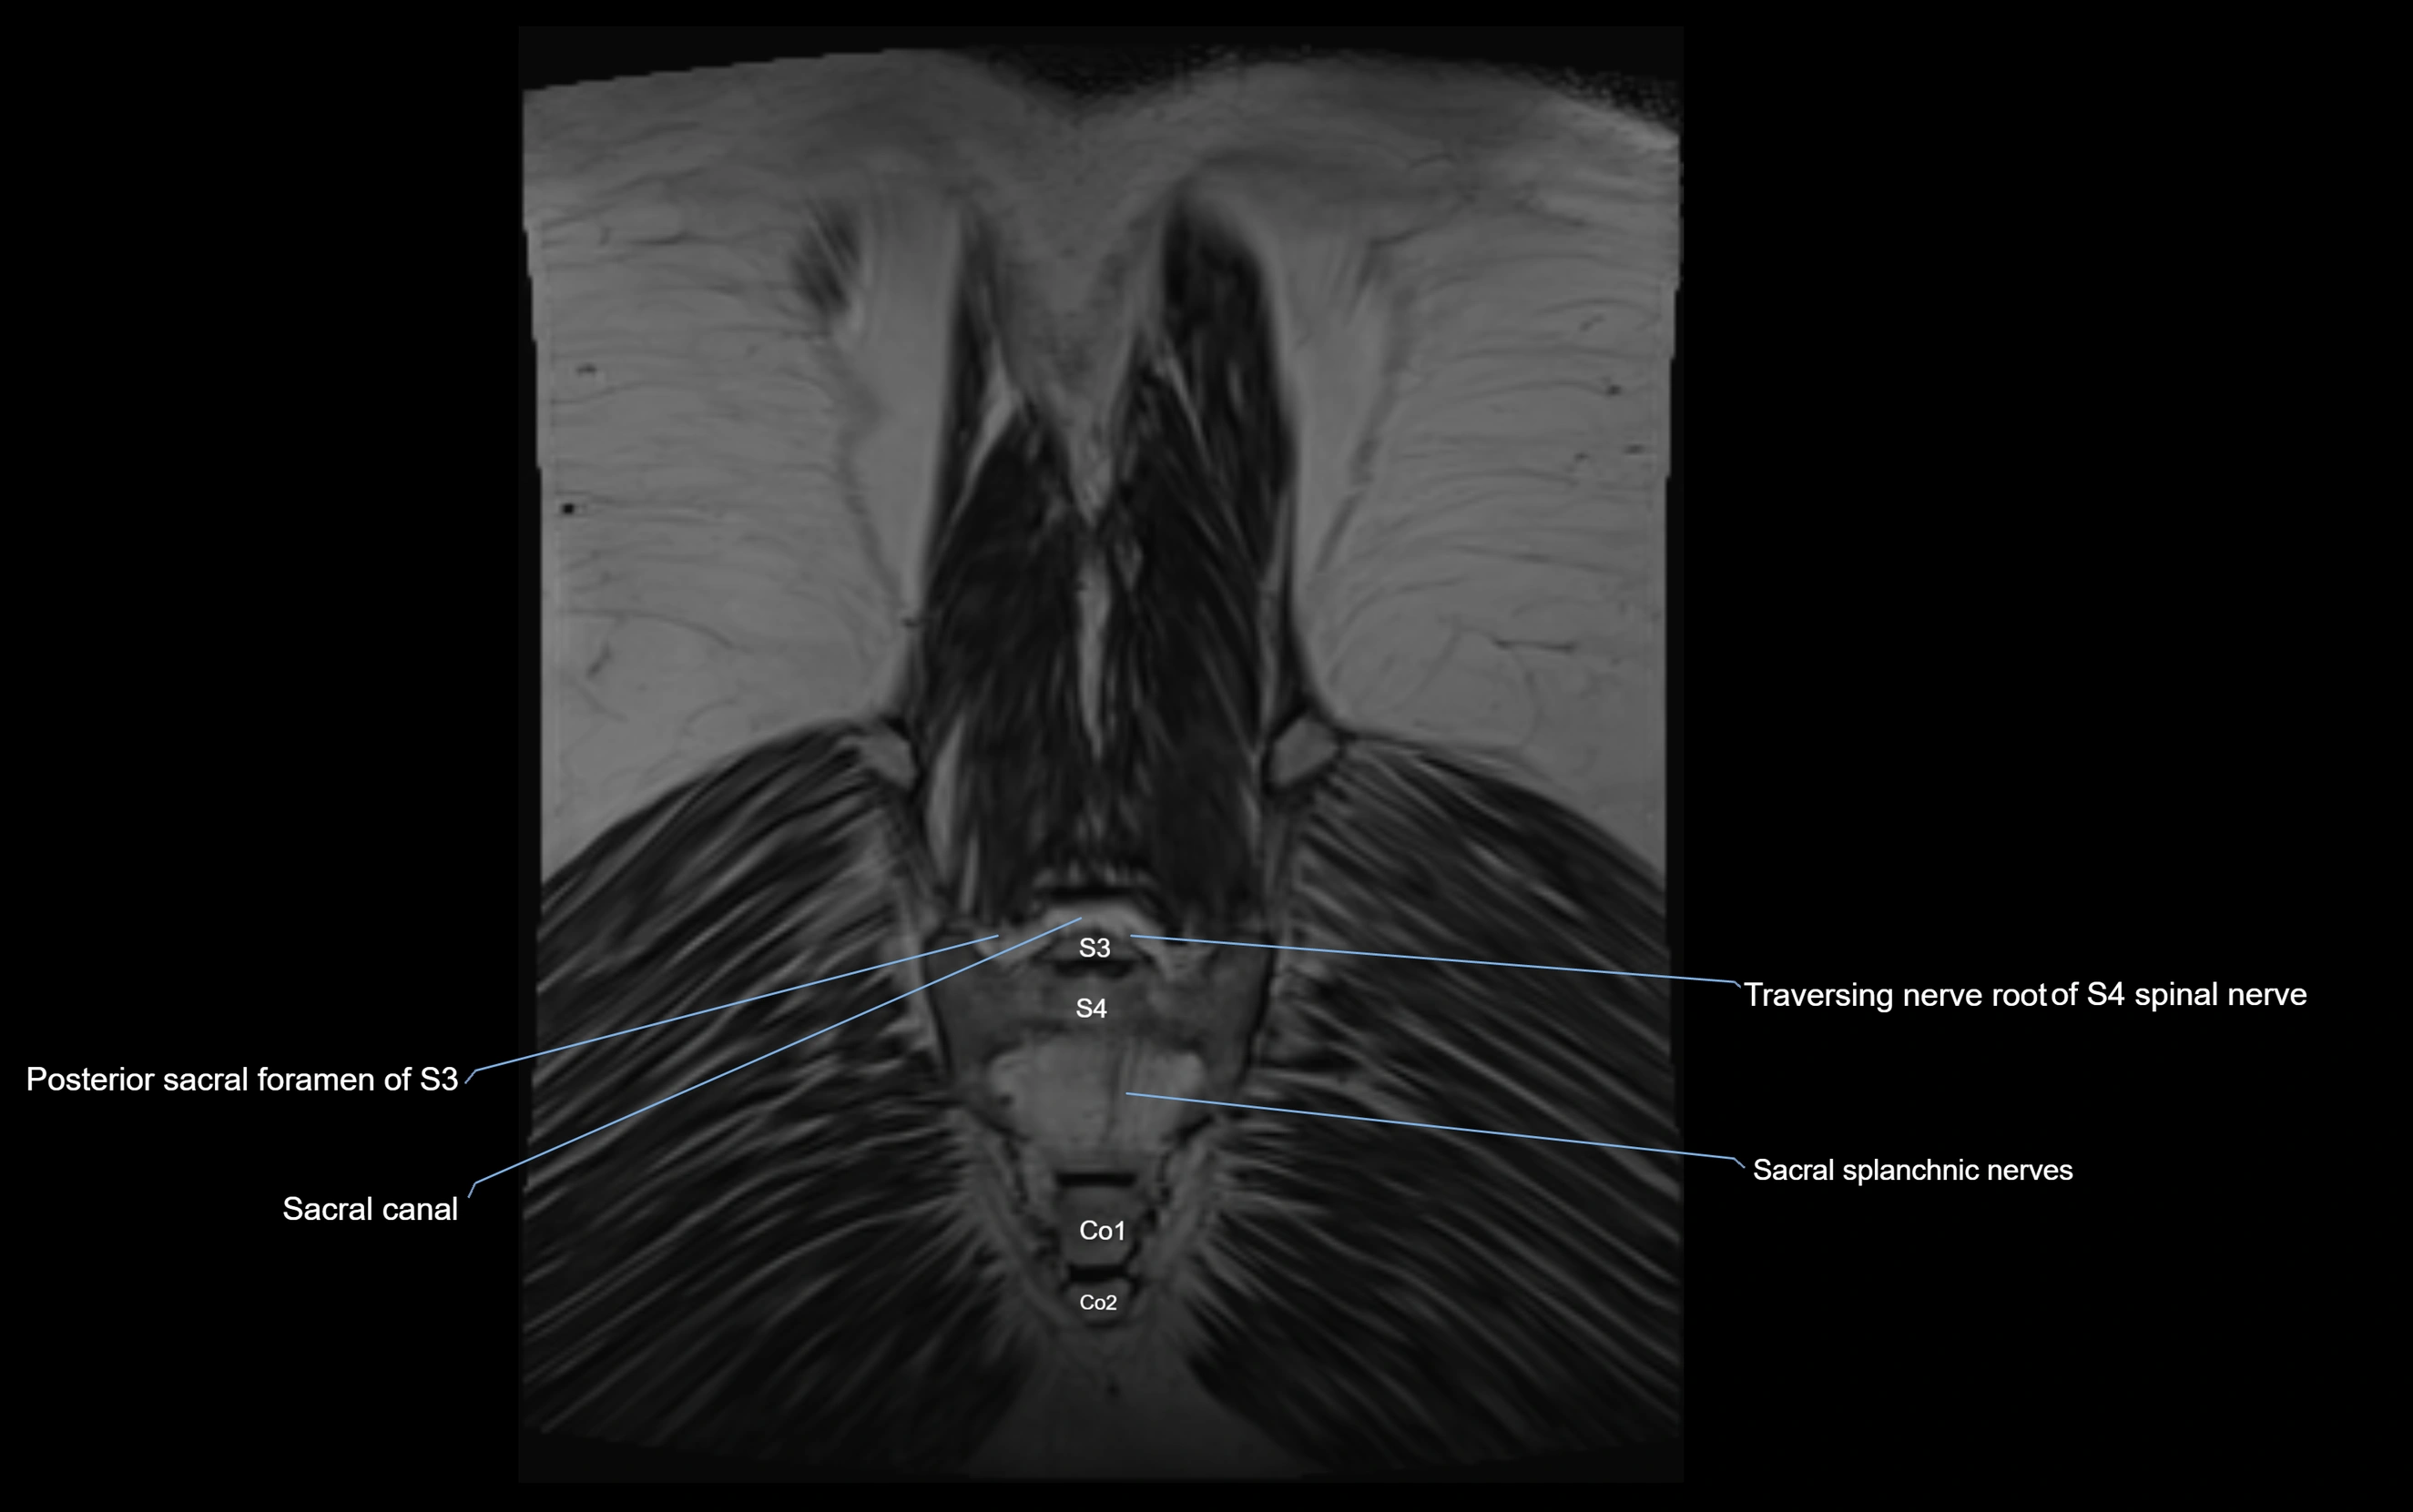

MRI image

image